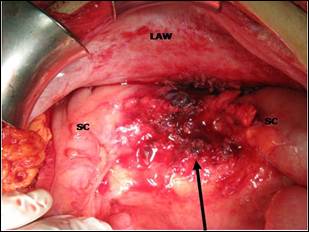

Figure 2: Arrow indicates the location of removed mass. It

was over sigmoid colon (SC) and lateral abdominal wall (LAW).